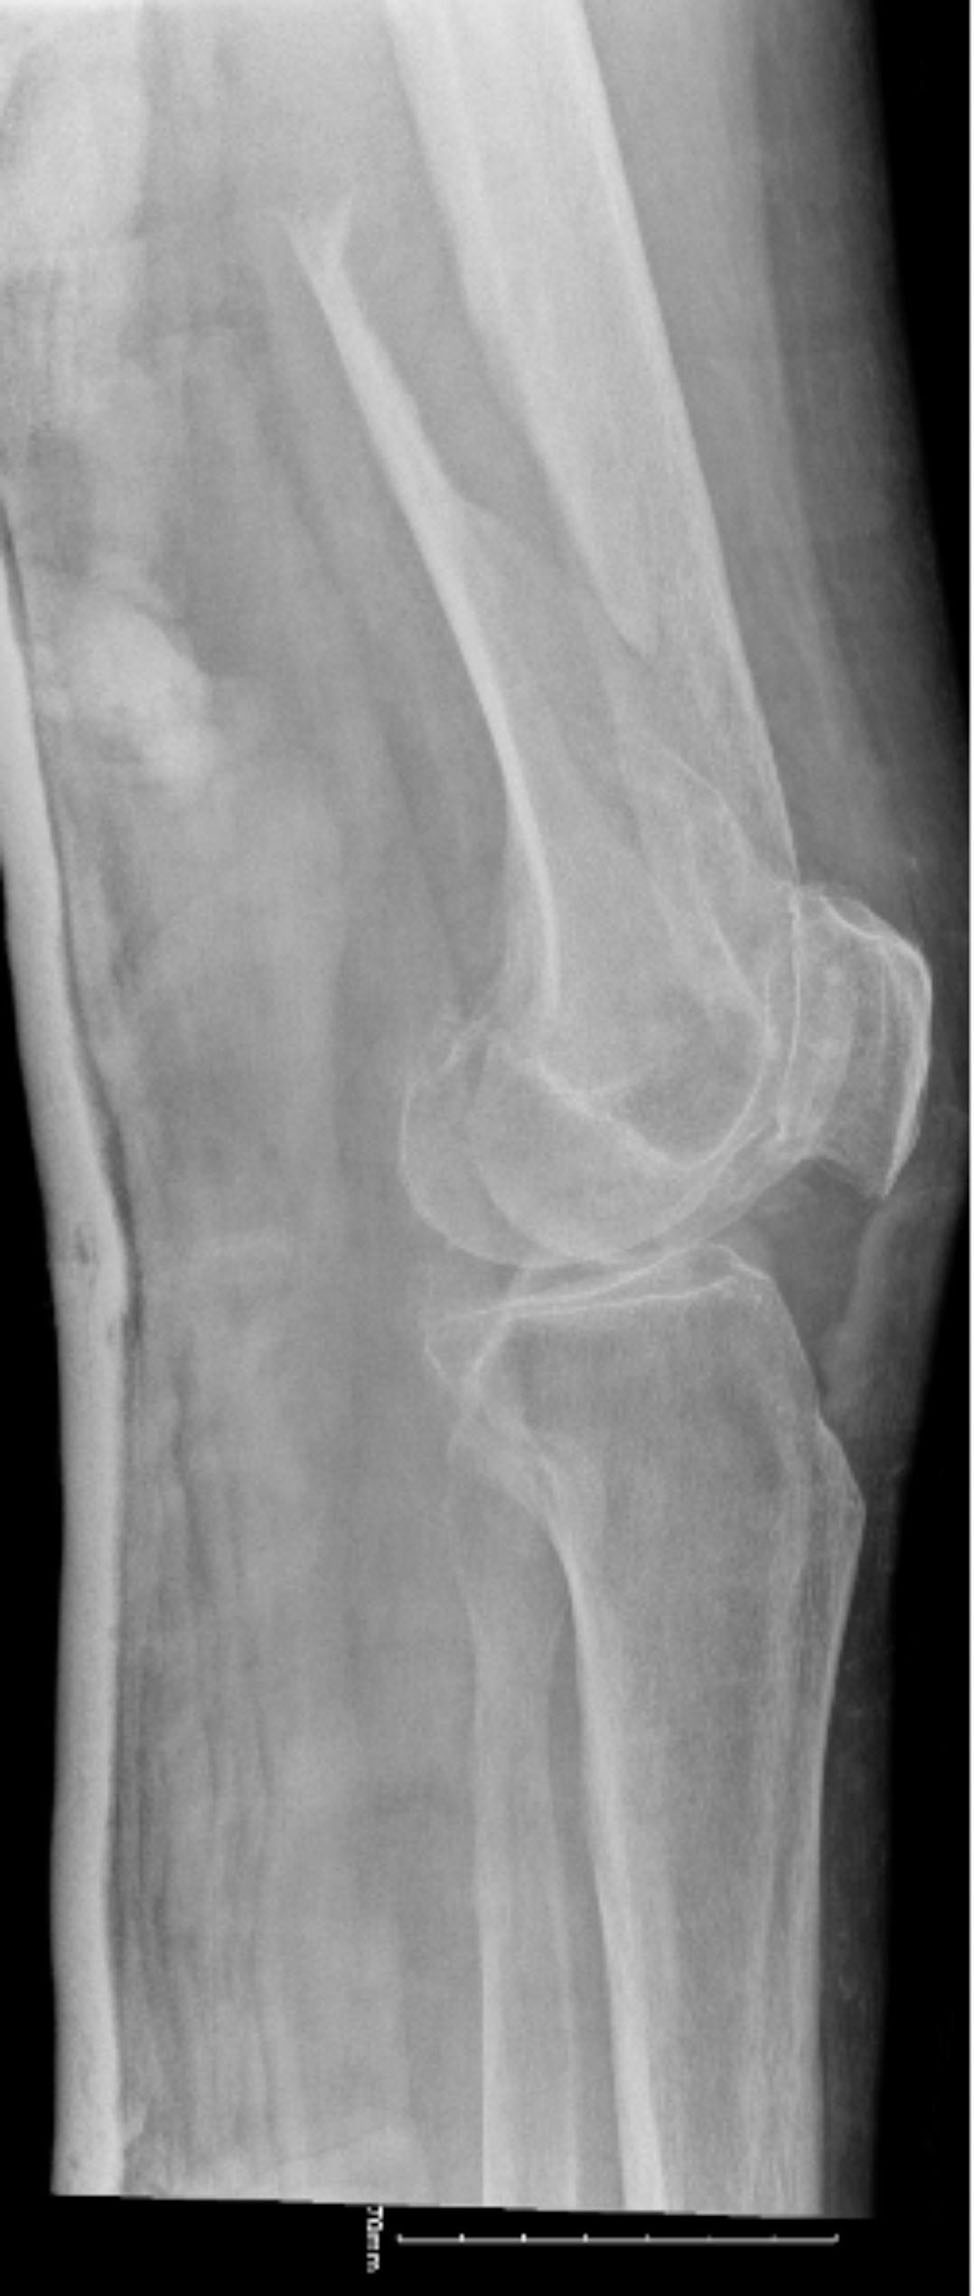

On a follow up call on day 2 (one day after first fitting, as per study protocol), the participant confirmed that she was wearing the airbag around her home, and that she had no problems in using or charging the device. On day 3, the participant, having fitted the airbag herself, attended her family doctor for a routine appointment. She would normally employ the use of a motorised mobility scooter when making this journey however on this day, her mobility scooter battery was not sufficiently charged so she attended by taxi instead. She opted for the use of two walking sticks for ease of travel by car instead of her 4-wheeled walking frame that she would normally use outdoors. On leaving the doctor’s premises, she walked outside to a waiting taxi. The taxi driver observed her standing on the pavement and that she was wearing “a belt” (the Hip’Guard) which appeared to be falling down from her waist onto her upper thighs. He called out to alert her as she seemed unaware of it having slipped down but she did not hear what he was saying, she later reported. She reported that she was focused solely on using her two walking sticks as she was fearful of falling, and was anxious to make her way safely to the car. As she stepped forward the Hip’Guard impeded her stride and she immediately fell, sustaining an oblique, comminuted fracture of the right distal femur (Fig. 1).

Fig. 1.

Distal femur fracture sustained by the participant

The fracture was successfully repaired with internal fixation however the post-operative clinical course was complicated by a post-operative haematoma requiring transfusion, recurrent bowel ileus, delirium and a prolonged hospitalisation (Fig. 4).

Fig. 4.

Post-operative x-rays following fixation of distal femur fracture